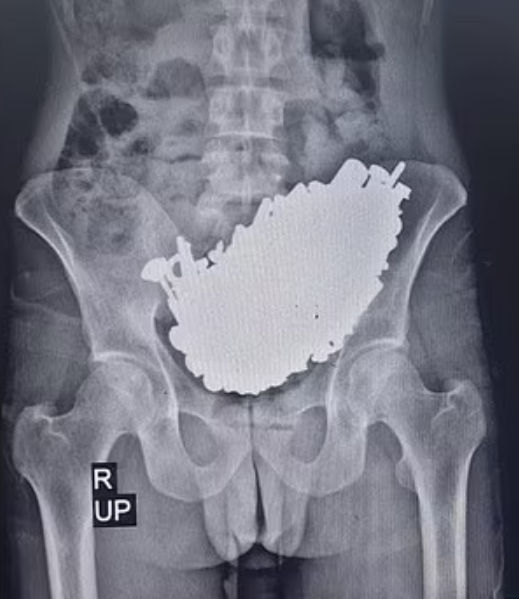

根據《TVBS新聞網》、《鏡週刊》報導,這起離譜案例被刊載於《醫學案例報告雜誌》(Journal of Medical Case Reports)當中,這位37歲的患者因為長期胃部疼痛,加上頻繁嘔吐,使得他完全沒辦法正常吃東西或喝水,於是趕緊到醫院掛急診。醫師替他進行X光檢查後,意外發現患者胃部竟然被超過3公斤的金屬製品塞滿。

醫療團隊隨即為患者安排手術,過程中總共從他體內挖出452件金屬異物,包含螺絲釘、螺帽、各種鑰匙、徽章以及石頭等物品。醫師初步推測,這些東西應該都是患者在過去90天左右陸續吃下肚的,慶幸患者術後復原狀況相當不錯。